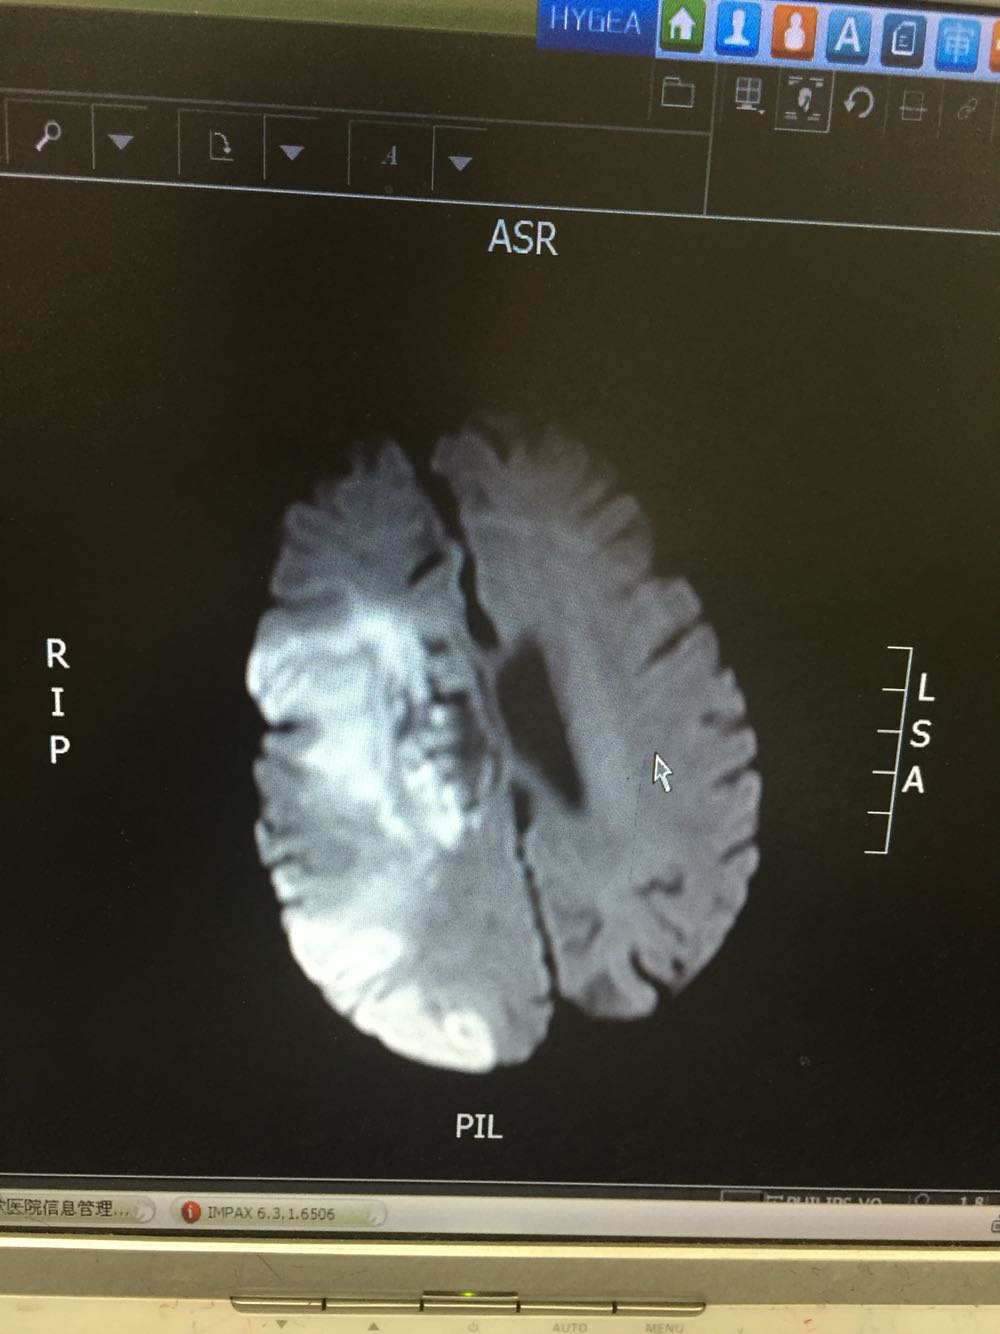

患者入院治疗后症状一度好转,左侧肢体肌力3级+,于入院后第二日病情突然加重,伴意识障碍,头DWI示:脑梗死伴脑出血 右侧大脑中动脉闭塞。停止当前治疗方案,脱水脑保护,营养神经对症治疗。入院后第5日复查头CT示:右侧大面积脑梗死,脑出血吸收期,伴左侧枕叶脑出血。患者左侧枕叶脑出血不好解释,能否是搬运及护理时外伤所致?